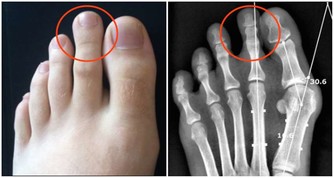

長期喝水不足,人的老化會加速,身體代謝會出狀況,造成腎臟機能不佳,尿酸高易引起腎結石、痛風發作,更常見泌尿道的感染發炎,例如膀胱炎、尿道炎等。如果反覆感染,會發生尿毒症,必須洗腎。所以千萬不要等到口渴才喝水!因為等到你覺得口渴時,身體多半已開始有脫水現象,隨時補充水分,才能喝水多健康。